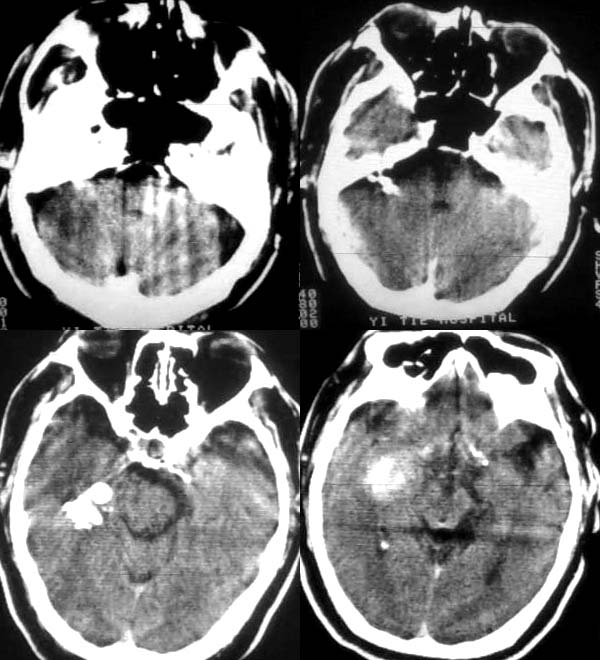

男53岁,既往有腔梗病史。突然昏迷。是多发脑出血吗?都是什么位置的?

右侧基底节区出血,双侧基底节区腔隙性脑梗塞,左侧基底节区脑软化灶。

右基底节区脑出血  双基底节区脑腔隙

那请问下在脑桥小脑角池的梭性高密度影是什么啊?跟对侧不对称啊!是不是考虑也是出血病灶啊!

脑桥小脑角的高密度灶与基底节区出血灶相连的   是一个出血灶延伸的

典型的右侧颞叶、基底节区原发性脑出血。

右侧颞叶、基底节区原发性脑出血;腔隙性脑梗塞;局限性脑萎缩。

1. 右侧基底节区出血,双侧基底节区腔隙性脑梗塞伴脑萎缩。

2.右侧桥小脑角区及右侧颞骨岩部内上缘高密度灶边缘太过锐利,不知ct值是多少?不太像出血。

右侧桥小脑角区及右侧颞骨岩部内上缘高密度灶边缘太过锐利,不知ct值是多少?不太像出血。应是运动性伪影。